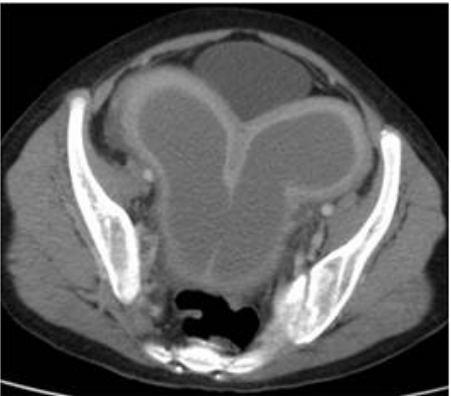

73.13歲女性病患,月經未來且下腹痛,故接受電腦斷層檢查,結果如下圖。其最有可能的診斷為何?

(A)子宮肌瘤(uterine myoma) (B)子宮內膜癌(endometrial cancer) (C)輸卵管卵巢膿瘍(tubo-ovarian abscess) (D)子宮融合異常合併處女膜未穿孔(uterine fusion abnormality with imperforated hymen)